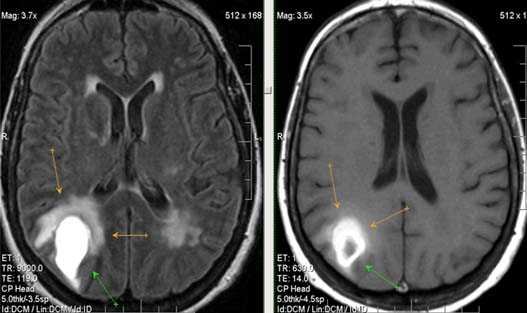

Валлеровская дегенерация вследствие инсульта в бассейне средней мозговой артерии в левом полушарии большого мозга. Р1_А1К-изображения (а, b) и Т2-ВИ в аксиальной плоскости (с). В зоне, кровоснабжаемой левой средней мозговой артерией, визуализируется кистозный дефект с глиозом (а). Определяется повышенная интенсивность сигнала от пирамидного пути в левой ножке мозга (b) и в продолговатом мозге слева (с).